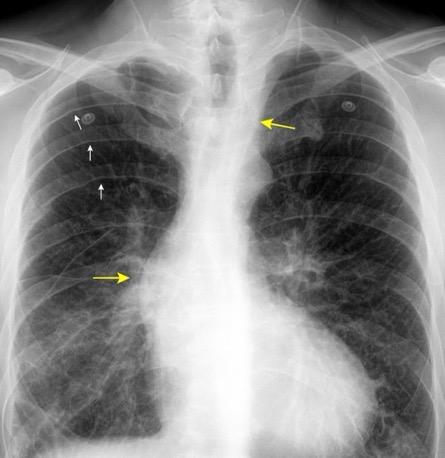

117. MASA MEDIASTÍNICA DE DENSIDAD AGUA

119. MASA MEDIASTÍNICA DE DENSIDAD GRASA

Atelectasias de lóbulos superiores por Radioterapia + lipomatosis en Ca. de pulmón radiado

Enfermedad pulmonar bilateral adosada.

Atelectasia “tumoral”

Empiema pleural mediastínico